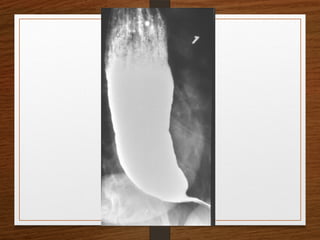

• Barium Swallow

• Achalasia

• Ca Esophagus

Contrast Films

• Barium Meal

• Barium Enema

• IVP

Barium Studies

Barium studies can demonstrate GI abnormalities in three ways

1. Mucosal relief views of the collapsed or partially collapsed

lumen obtained with a small volume of barium.

• particularly useful for showing abnormalities involving the

submucosa, such as esophageal varices.

2. Single-contrast views of the filled lumen obtained with a

large volume of low-density barium

• These views enable visualization of contour abnormalities,

strictures, and large polypoid defects.

3. Double-contrast views obtained after the mucosal surface

has been coated with a thin layer of high-density barium

and the lumen has been distended with gas

• These views enable visualization of subtle mucosal lesions, such as

the early changes of inflammatory bowel disease and early

neoplastic lesions

• Barium suspensions for single-contrast studies

should be of moderate density (50%-100% w/v)

when not diluted.

• For the double-contrast examination, we use high-

density 250% w/v barium

Contrast Films • BariumSwallow • Barium Meal • Barium Enema • IVP

Barium Studies Barium studiescan demonstrate GI abnormalities in three ways 1. Mucosal relief views of the collapsed or partially collapsed lumen obtained with a small volume of barium. • particularly useful for showing abnormalities involving the submucosa, such as esophageal varices. 2. Single-contrast views of the filled lumen obtained with a large volume of low-density barium • These views enable visualization of contour abnormalities, strictures, and large polypoid defects. 3. Double-contrast views obtained after the mucosal surface has been coated with a thin layer of high-density barium and the lumen has been distended with gas • These views enable visualization of subtle mucosal lesions, such as the early changes of inflammatory bowel disease and early neoplastic lesions

• Barium suspensionsfor single-contrast studies should be of moderate density (50%-100% w/v) when not diluted. • For the double-contrast examination, we use high- density 250% w/v barium